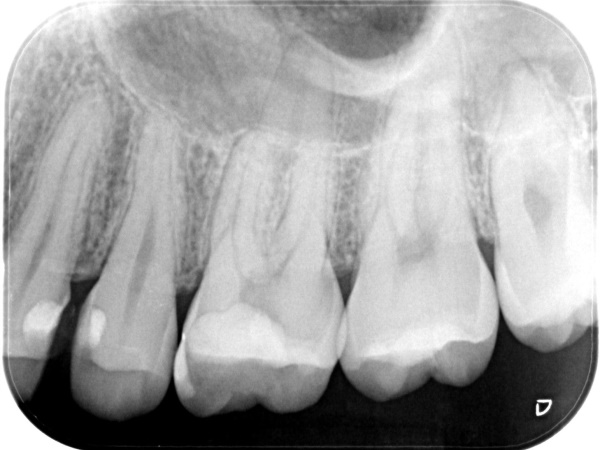

初診時